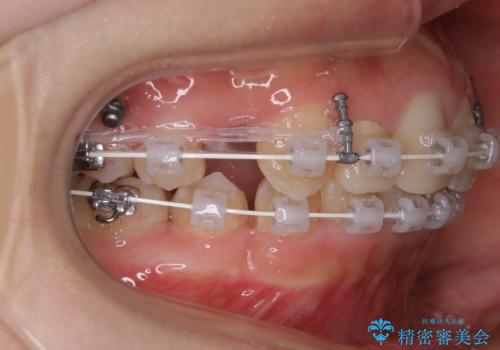

- ワイヤー矯正 審美装置

矯正治療で根の向きも修正したため、左右対称に審美的なセラミックを入れることができました。

右下の隙間を閉じるため、歯の数を合わせるため、右上の小臼歯を一本抜歯しています。